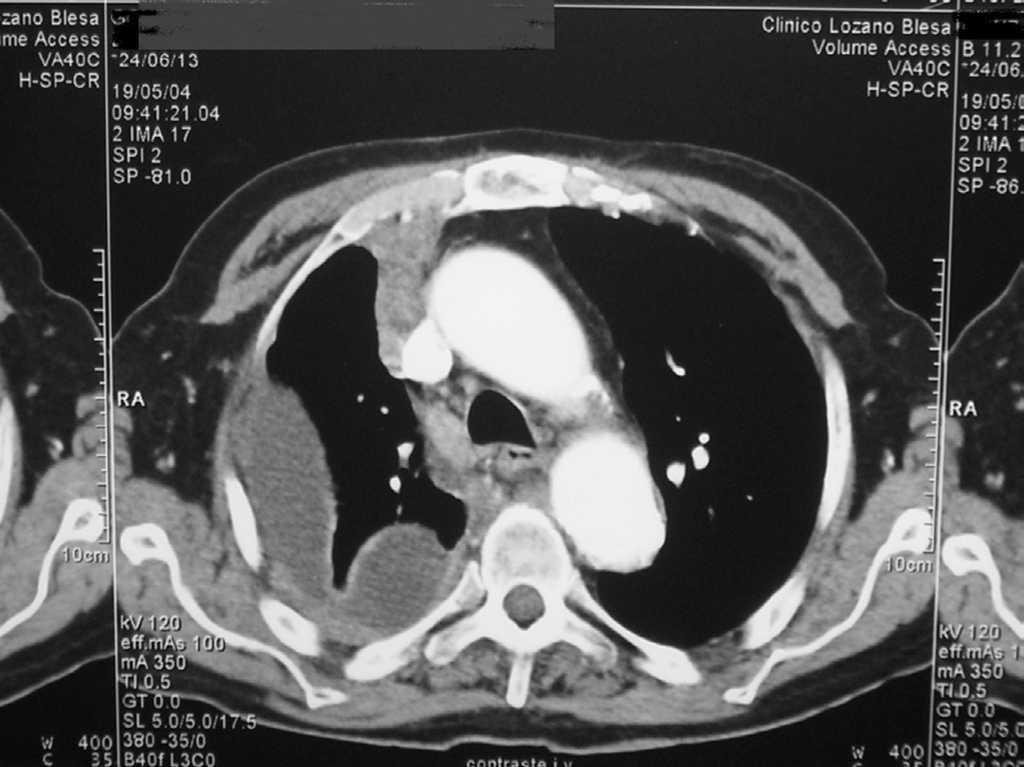

Ante los hallazgos físicos y analíticos comentados, se decidió realizar una tomografía computarizada (TC) toracoabdominal, que mostró un parénquima pulmonar colapsado por derrame pleural parcialmente encapsulado, con engrosamiento de pleura parietal de hasta 15 mm que parecía infiltrar la pared torácica, y abundante líquido ascítico tabicado con aumento de densidad en epiplón y peritoneo parietal (figs.1 y 2).

Figura 1.TC Toracoabdominal.

La TC toracoabdominal orientó el diagnóstico hacia un mesotelioma --neoplasia muy poco frecuente en su localización abdominal, muy relacionada con el asbesto9--, sin descartar adenocarcinoma pleural metastásico. El antecedente del contacto con asbesto no se pudo comprobar en la historia de nuestro paciente. En diversos estudios se ha observado un elevado porcentaje de casos sin historia de exposición a asbesto, como el estudio mexicano que no lo demostró en un 80% de 45 casos de mesotelioma maligno10,11.

La sospecha clínica de mesotelioma estaba justificada en este paciente, ya que el mesotelioma maligno es la tumoración maligna primaria más frecuente de la pleura12, y su manifestación más frecuente es el dolor torácico seguido de disnea; las alteraciones radiológicas más frecuentes son el derrame pleural generalmente unilateral y la masa o engrosamiento pleural. En el mesotelioma peritoneal es la ascitis, signo también presente en nuestro enfermo.